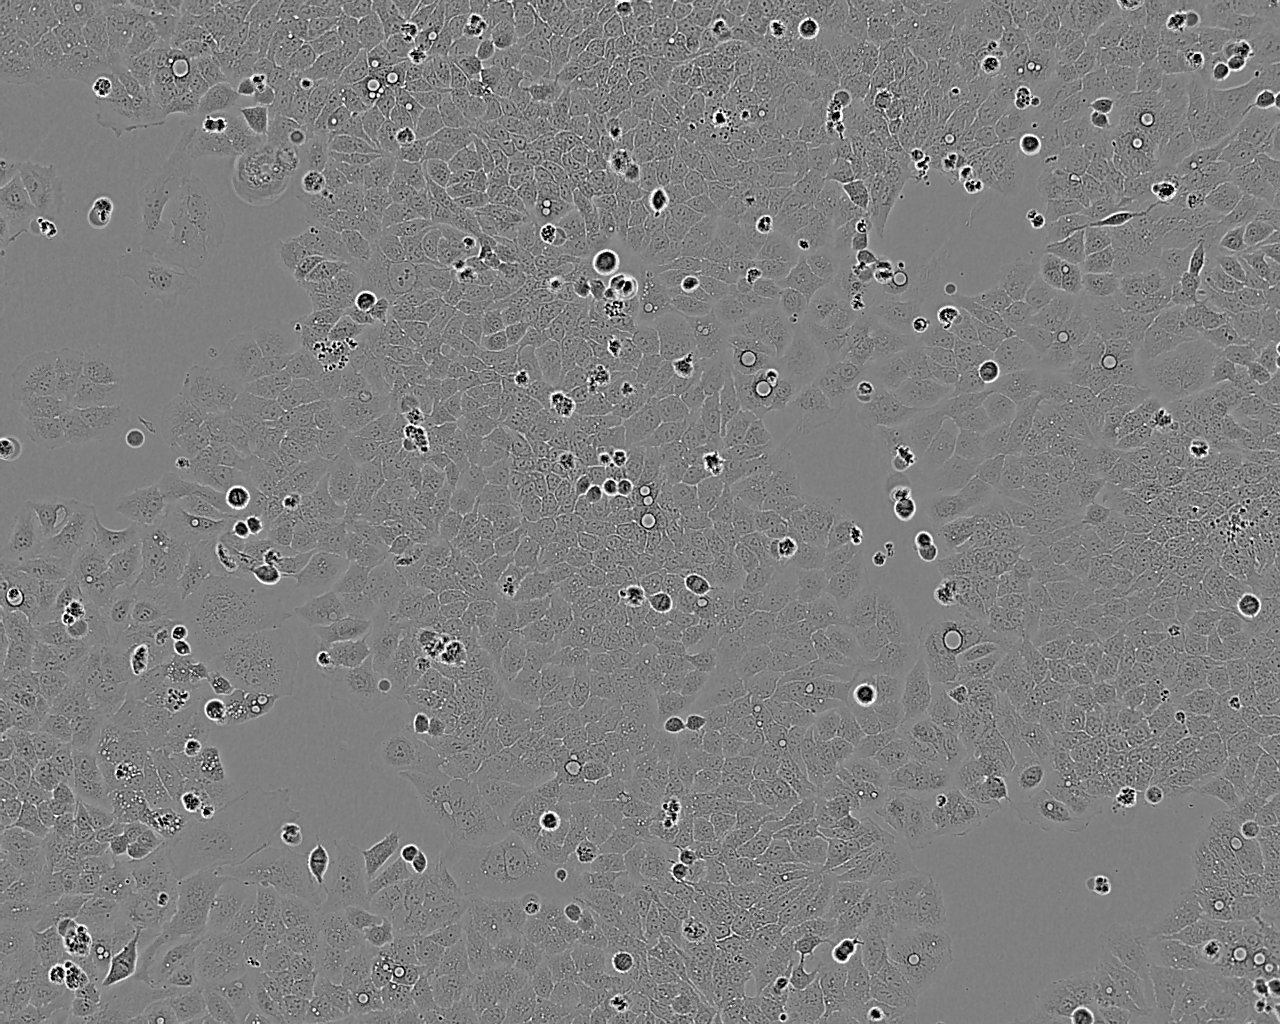

细胞背景资料:皮肤鳞癌;男性

细胞形态:上皮细胞样

细胞生长:贴壁

细胞生长特性:贴壁